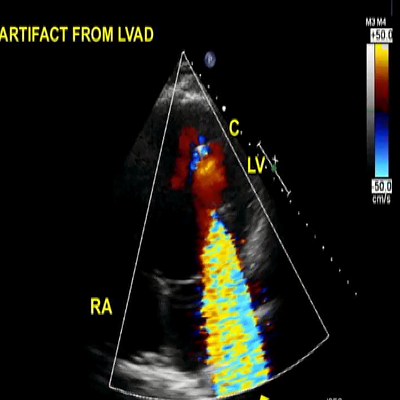

This is an adult patient who underwent left ventricular assist device (LVAD) placement for dilated cardiomyopathy and heart failure.